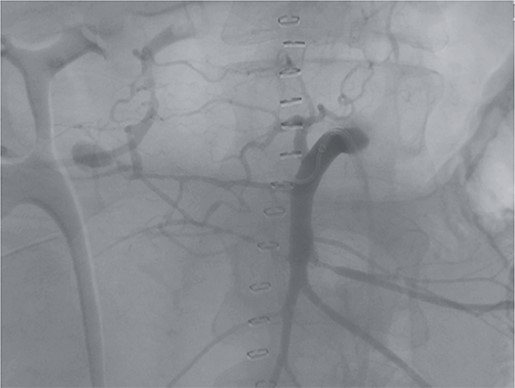

However, on the 16th day following the initial surgery, there was another active bleeding from the pancreaticoduodenal artery, distal to the previously placed coil. This bleeding was also managed interventionally (Figs 4 and 5).

Angiography showing another aneurysm with active bleeding, proximally to the previously coiled site.

Postinterventional angiography, after interventional bleeding control, using coiling.